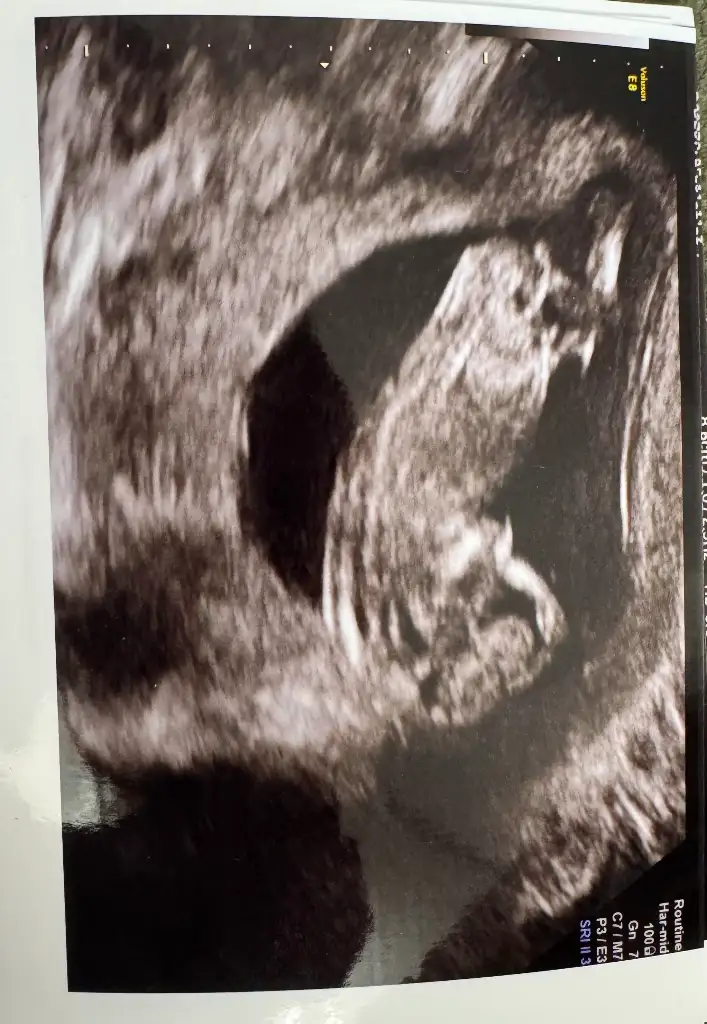

kızlaar bugün doktor kontrolüm vardı çok şükür herşey yolunda, fetal için kan verdik 1 haftaya çıkacakmış sonuç. Doktorum cinsiyette bi tahmini olduğunu söyledi ama organizasyon yapmak istediğimizi söyleyince fetali bekleyelim net olsun dedi. Ama eğlence olsun ultrason fotoğrafından tahmin eder misiniz sizce kız mı erkek mii

Eklentiler

• IMG_4552.webp

44,9 KB · Görüntüleme: 0

• IMG_4551.webp

23,3 KB · Görüntüleme: 0

• IMG_4547.webp

35,8 KB · Görüntüleme: 0